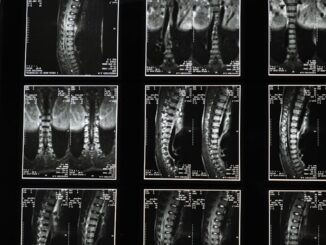

Summary Artificial intelligence (AI) is rapidly transforming healthcare, offering benefits like improved diagnostics, personalized treatments, and streamlined administration. This article explores the latest advancements in AI integration within the medical field, highlighting its potential to […]